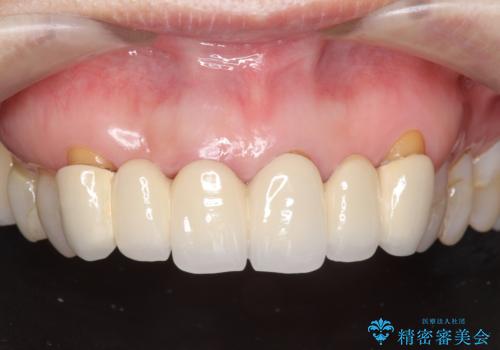

不自然な前歯ブリッジ ジルコニアブリッジによるやり替え

- 20年前に入れたブリッジの見た目の改善を求めて来院されました。

丁寧に現在装着されているブリッジを除去後、精度の高いジルコニアブリッジで審美性の改善を計画します。

- 66万円(仮歯・ジルコニアクラウン×6)費用は治療当時の料金となります